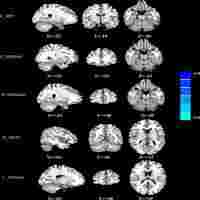

| Abstract | Background. This study aimed to evaluate the usability of SWI in assessment of brain iron to detect cognitive dysfunction in patients with chronic mild traumatic brain injury (mTBI). Methods. 39 patients with mTBI and 37 normal controls were given the Mini-Mental State Examination (MMSE) and underwent SWI scanning at least 6 months after injury. Angle radian values were calculated with phase images. The angle radian values were compared between groups using analysis of covariance, and their association with MMSE scores was analyzed using Spearman correlations. Results. Significantly higher angle radian values (p < 0.05) were found in the head of the caudate nucleus, the lenticular nucleus, the hippocampus, the thalamus, the right substantia nigra, the red nucleus, and the splenium of the corpus callosum (SCC) in the mTBI group, compared to the control group. MMSE scores were negatively correlated with angle radian values in the right substantia nigra (r = −0.685, p < 0.001). Conclusions. Patients with chronic mTBI might have abnormally high accumulations of iron, and their MMSE scores are negatively associated with angle radian values in the right substantia nigra, suggesting a role of SWI in the assessment of cognitive impairments of these patients. |